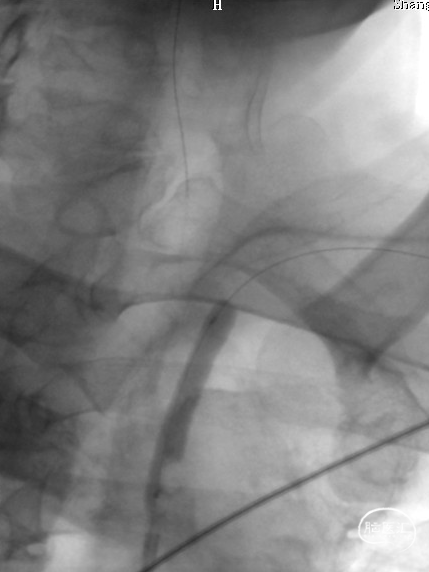

0.018*300cm 外周导丝至左肱动脉,0.014*200cm 通桥北斗SS™神经血管导丝超选至左椎V2段远端。

沿0.018*300cm 外周导丝送入6*40 外周球囊送至左侧锁骨下动脉狭窄处,压力泵逐渐加压到6atm。

撤出球囊后见残余狭窄40%。

再次沿0.018*300cm 外周导丝送入6*40 外周球囊达LSub狭窄部位,压力泵逐渐加压到8atm,见残余狭窄20%。

立即行Dyna-CT,未见脑出血表现,立即予以尼卡地平及尼莫地平降压,动脉静推负荷量替罗非班。

造影见LV闭塞,立即沿0.014*200cm 通桥北斗SS™神经血管导丝置入3mm*16mm 药物球扩支架至LV1。

压力泵逐渐加压球扩支架到8atm, 支架打开良好,造影示残余狭窄0%。